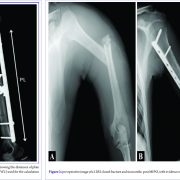

MIPO for Humeral Shaft Fractures: Correlation between Radiographic, DASH, and SF-12 results